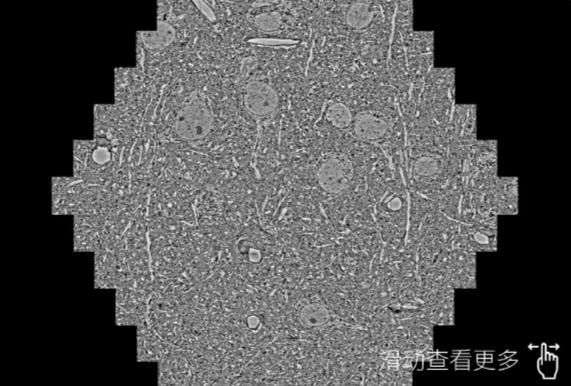

鼠脑切片。左图使用银川蔡司银川扫描电镜MultiSEM706对165μmx143pm面积区域成像,耗时仅需1.5秒。右图为鼠脑切片中30μm区域放大效果。样品由芝加哥大学B.Kasthuri提供。